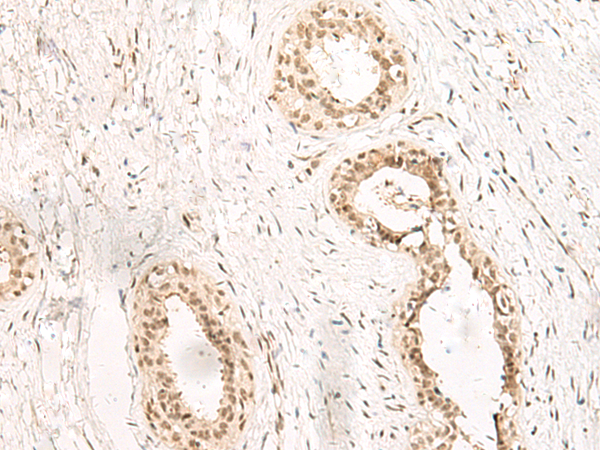

分类: 科研抗体货号: P13516别名: GPCR; bA86F4.3应用: WB,IHC反应种属: Human